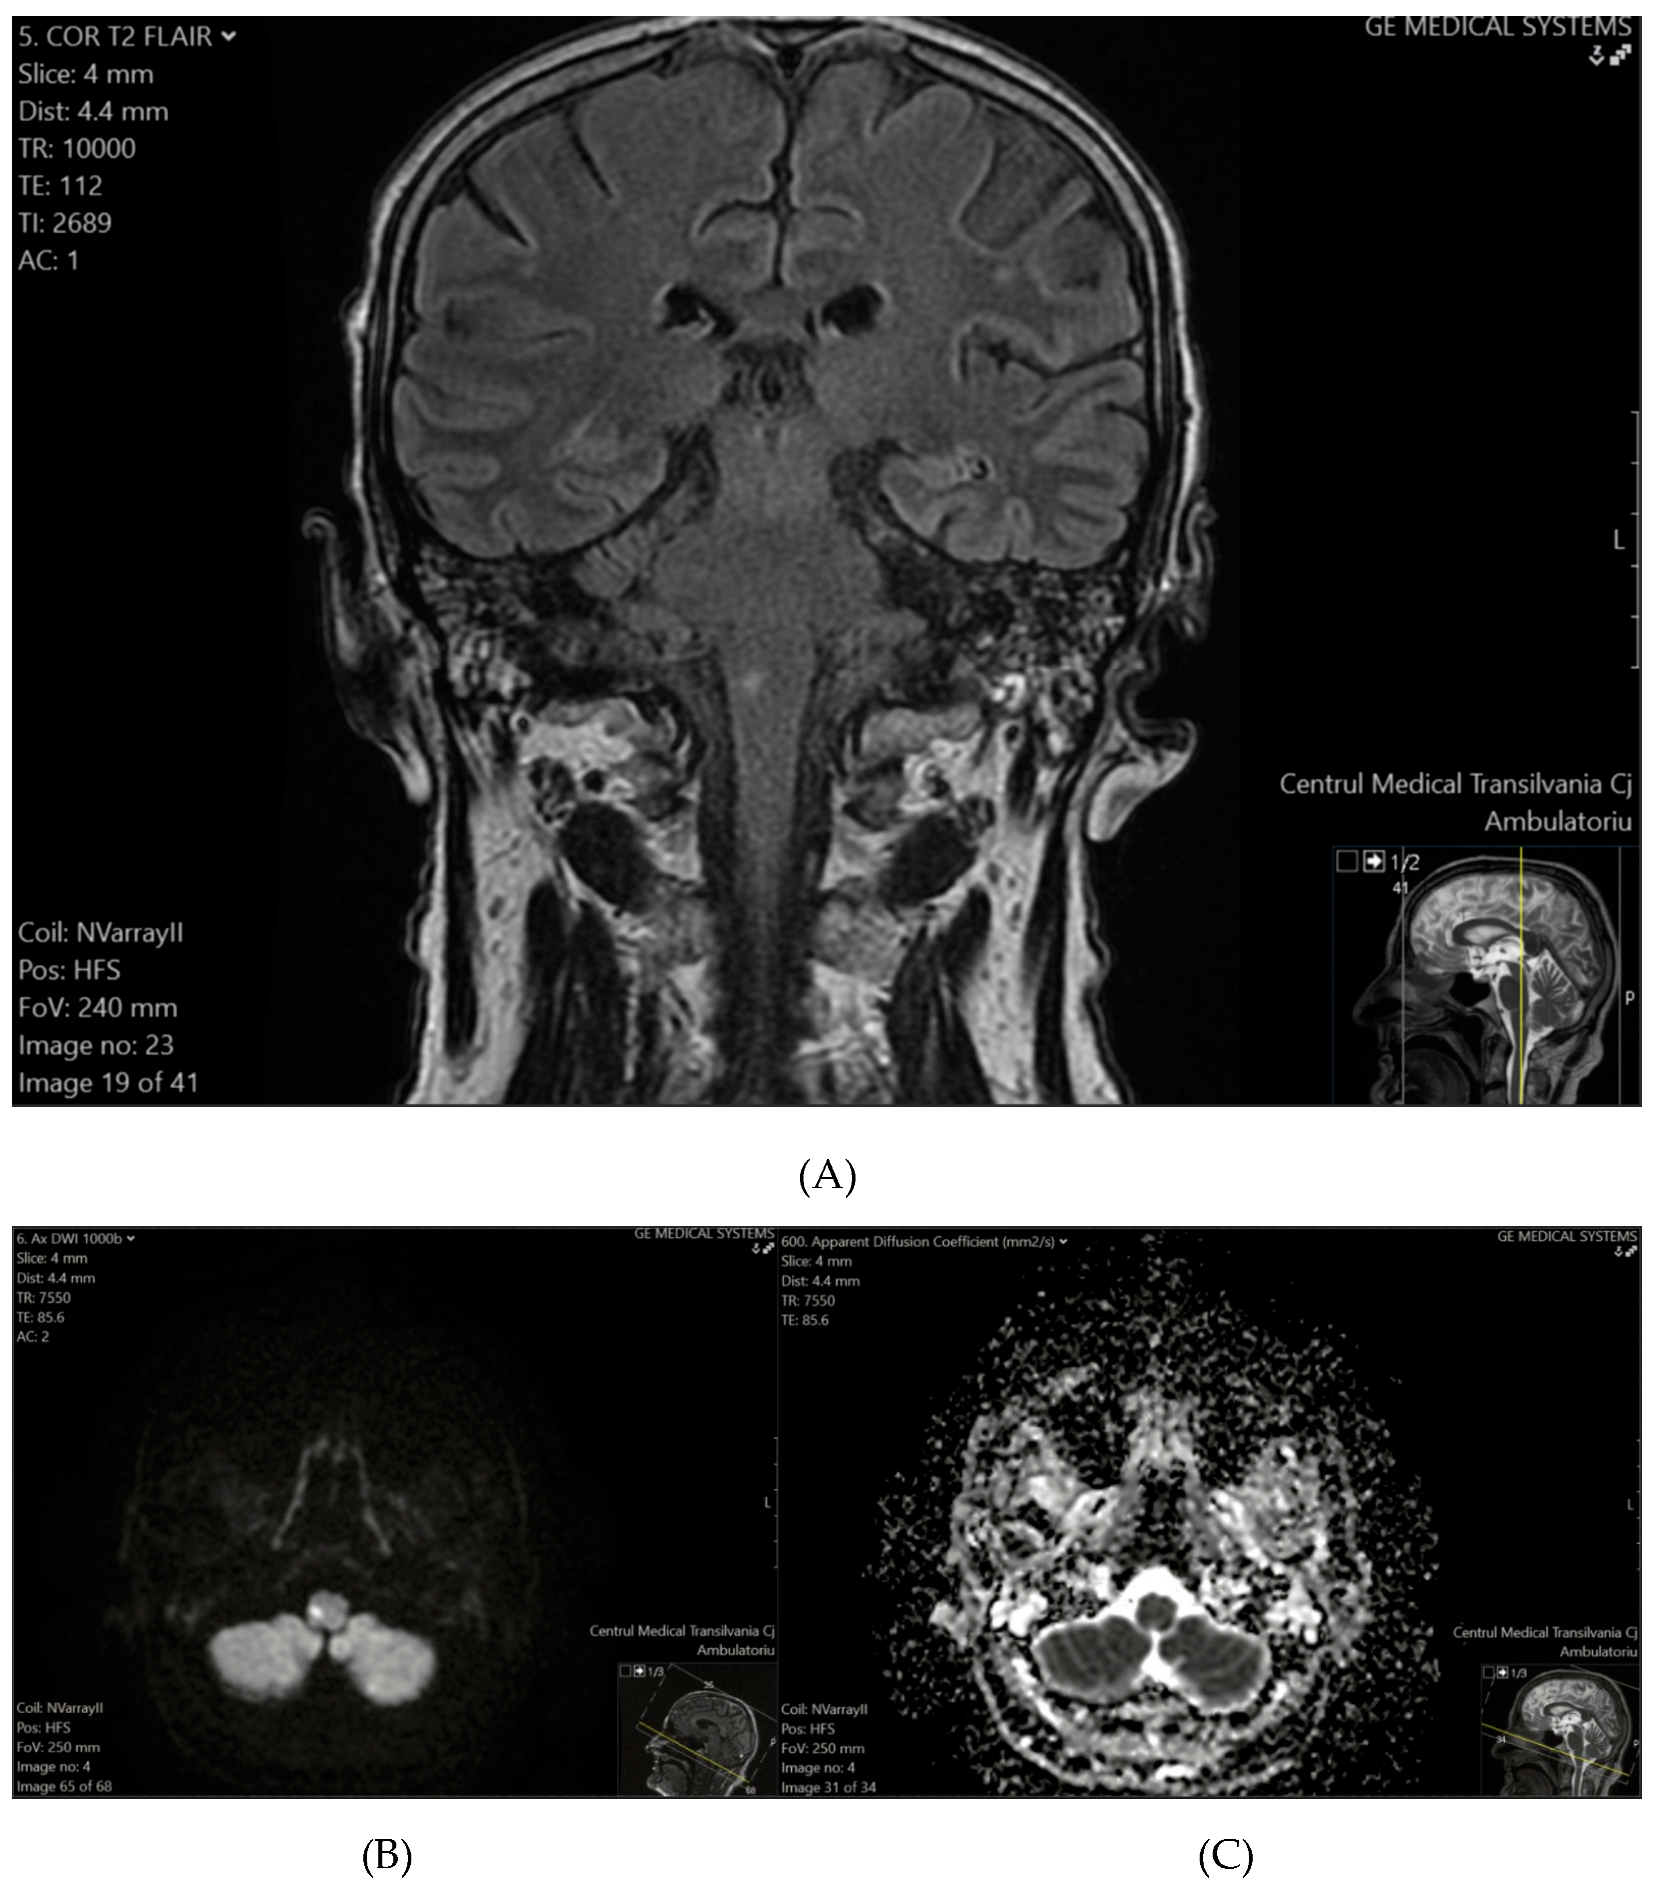

Patient 2 exhibited a hyperintense lesion in the right thalamus and the posterior limb of the internal capsule on T2-FLAIR (Figure 2A), with restricted diffusion on DWI and ADC sequences (Figure 2B,C), consistent with a recent ischemic event.

Figure 2. (A) (top) T2-FLAIR shows a hyperintense lesion in the right thalamus and the posterior limb of the internal capsule. (B) (bottom-left), (C) (bottom-right) DWI (B) and ADC (C) sequences confirm diffusion restriction, consistent with a recent ischemic event.